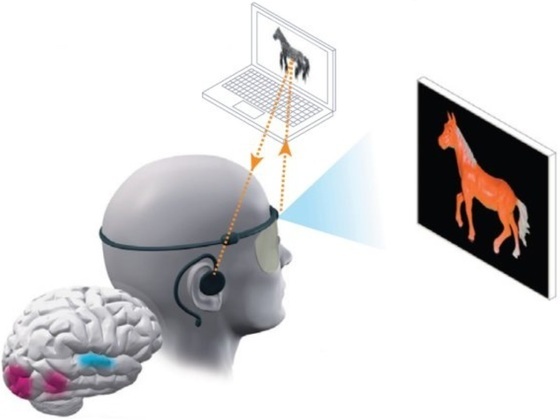

Но после 16 лет тьмы Гомез предоставили шестимесячное окно, во время которого она могла видеть подобие окружающего мира в очень низком разрешении, представленное жёлто-белыми точками и фигурами. Это стало возможным благодаря модифицированным очкам с крохотной камерой. Устройство подключено к компьютеру, обрабатывающему картинку в реальном времени и превращающему её в электрические сигналы. Свисающий с потолка кабель соединяет систему с разъёмом, встроенным в затылок Гомез, подключённому к имплантату со 100 контактами, помещённому в зрительную кору задней части её мозга.